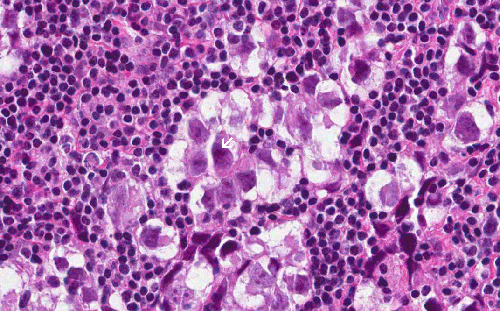

Hematoxylin & eosin

The nuclear details of both the germinoma cells and reactive lymphocytes are well demonstrated in this high-magnification photo. Note the large and prominent nucleoli (arrow).

• The tumor is composed of large, polygonal cells with prominent nucleoli. These tumor cells also have only a small amount of cytoplasm. The bulk of the cell is occupied by the nucleus. Although enlarged, the tumor cells are rather homogenous in size (Area 2).

• The tumor cells are surrounded by numerous lymphocytes. These are reactive lymphocytes and are mostly composed of T-cells.